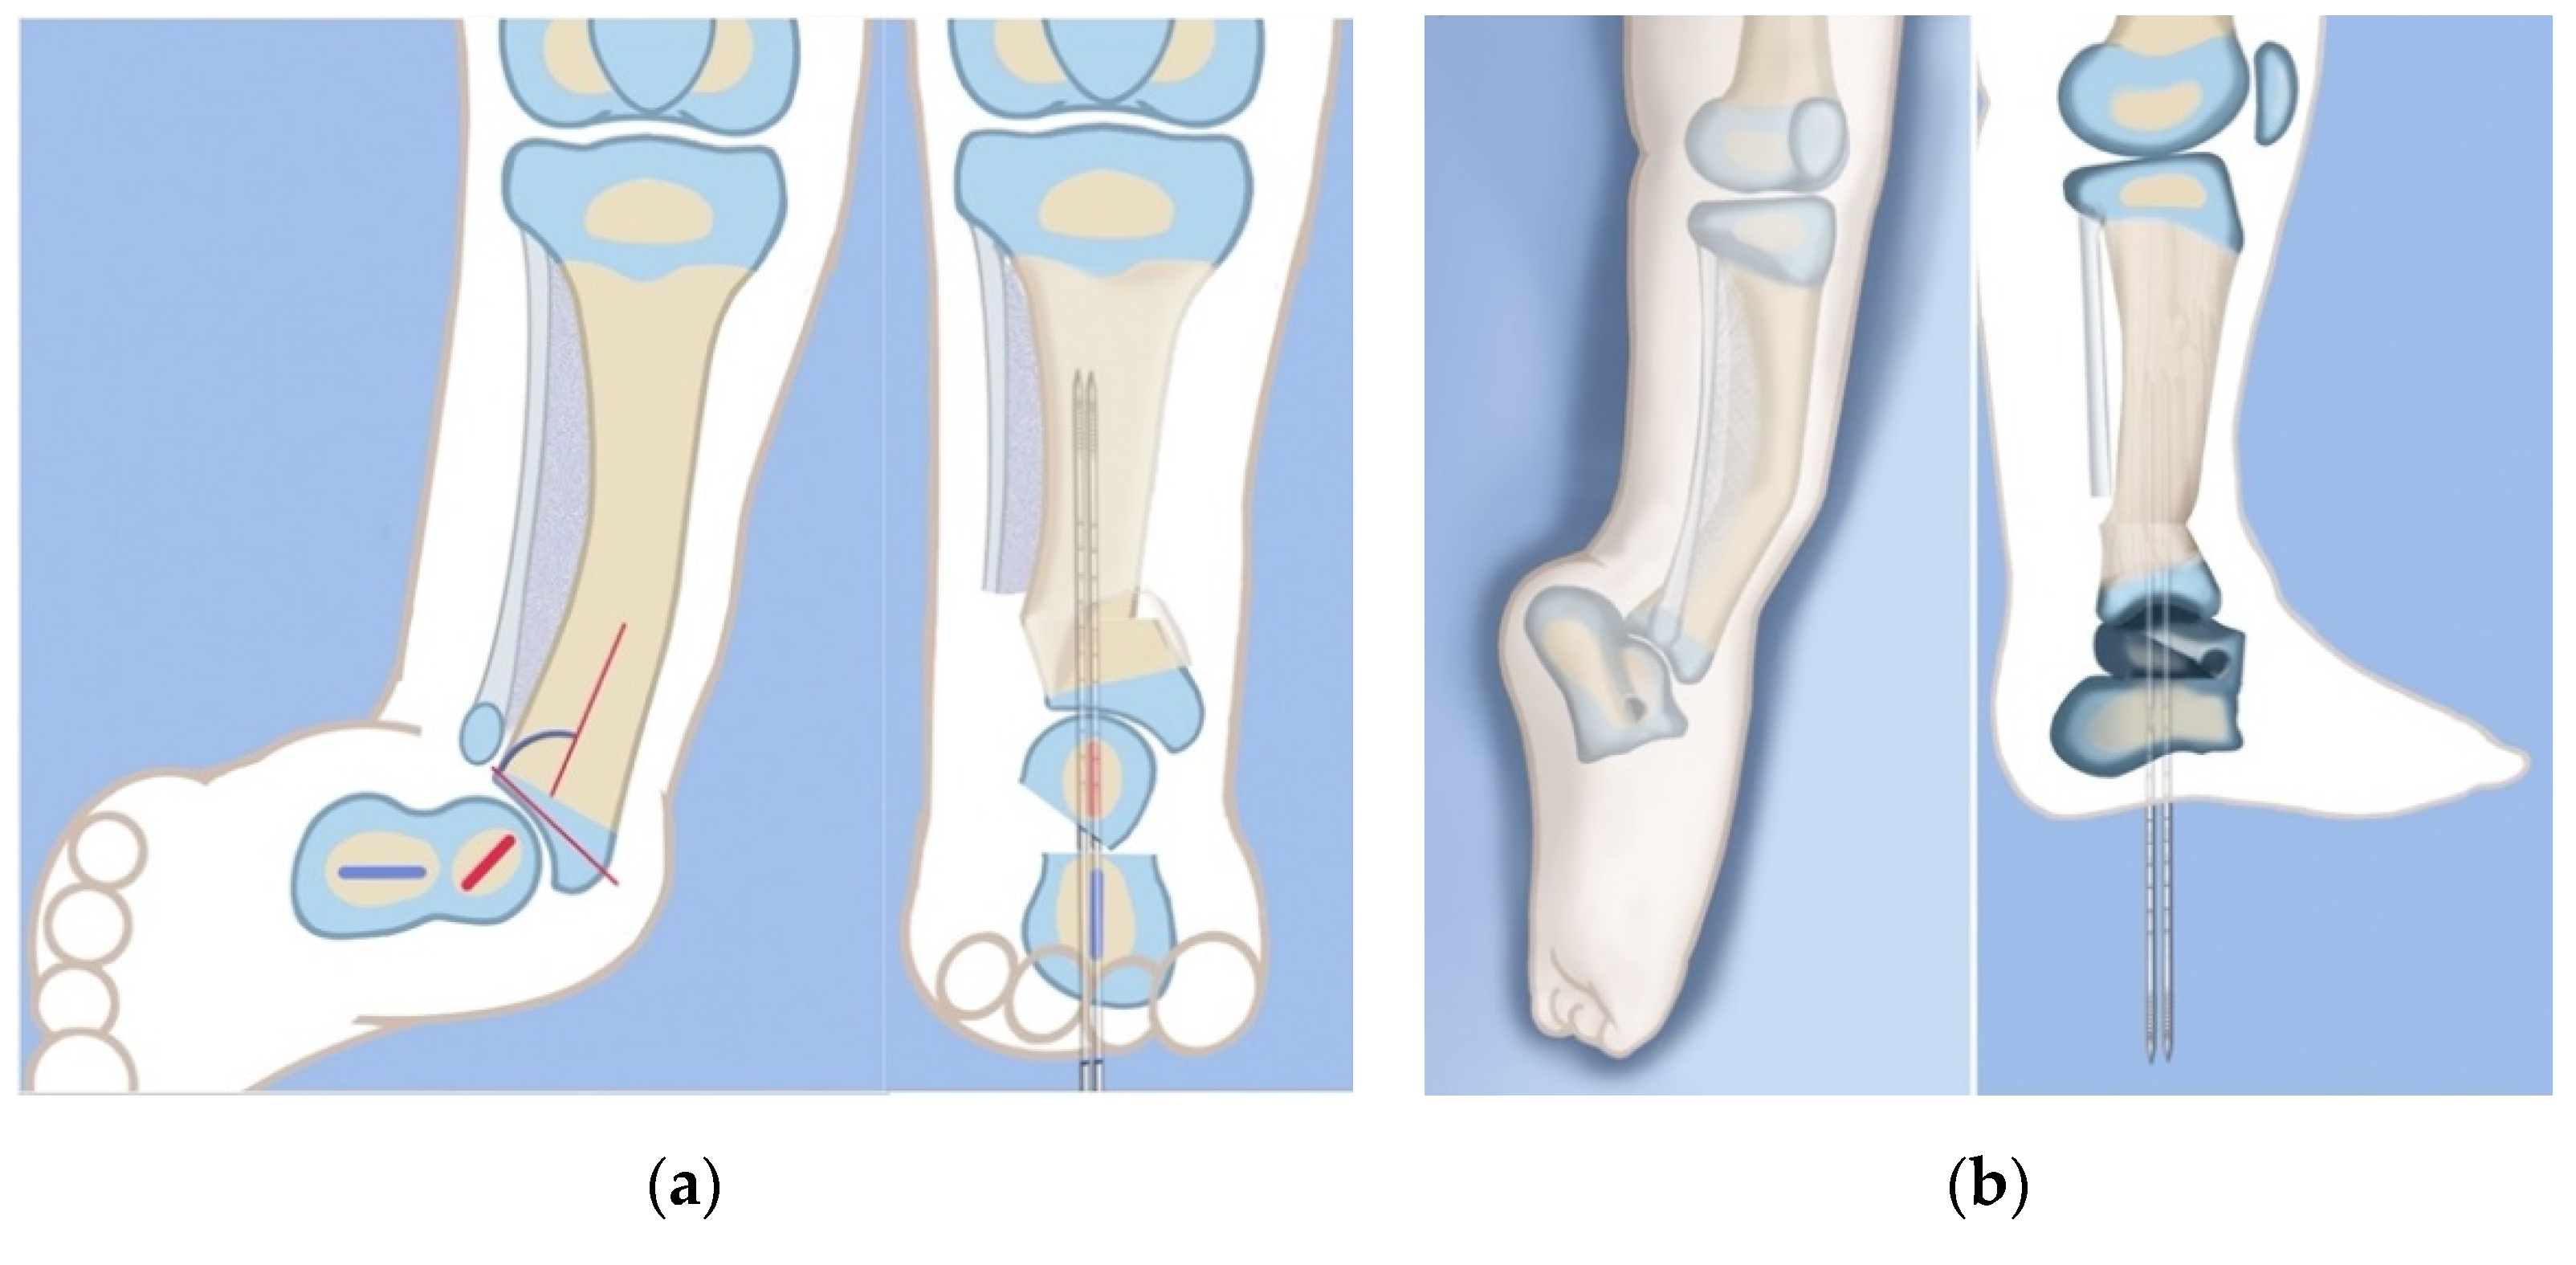

Figure 5.

Illustrations of before (left) and after (right) the SUPERankle procedure (Systematic Utilitarian Procedure for Extremity Reconstruction) procedure for fixed equinovalgus deformity of Paley type 3C FH from AP (a) and lateral (b) views. The main elements of this procedure are the subtalar angulation translation osteotomy and the supramalleolar varus-extension with shortening osteotomy.